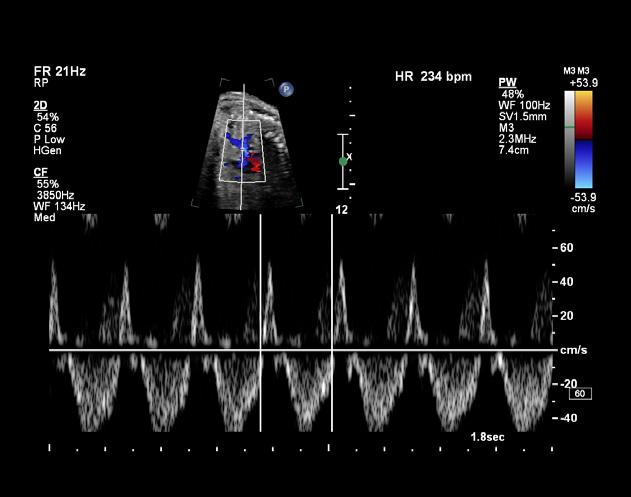

La tétralogie de Fallot est la plus fréquente des cardiopathies congénitales cyanogènes, représentant près de 8 % d’entre elles. Cette malformation tire son nom d’Étienne-Louis Arthur Fallot, qui l’a décrite en 1888.

La tétralogie de Fallot se caractérise par quatre anomalies distinctes, comme ÉtienneLouis Fallot, anatomopathologiste, les avait observées lors d’autopsies. En réalité, deux de ces anomalies suffisent à expliquer la physiopathologie de cette malformation, les deux autres n’étant que des conséquences. Cette introduction vise à offrir un aperçu des caractéristiques cliniques, des défis diagnostiques et des approches thérapeutiques actuelles de cette pathologie (figure 1 ).

Signes et symptômes

Nouveau-né et nourrisson

À la naissance, le nouveau-né est souvent bien coloré, rose, et ne présente pas de gêne particulière. Cependant, la présence d’un souffle cardiaque systolique, perçu dès l’auscultation en salle d’accouchement, attire l’attention. Un souffle d’apparition précoce nécessite une échocardiographie d’urgence.